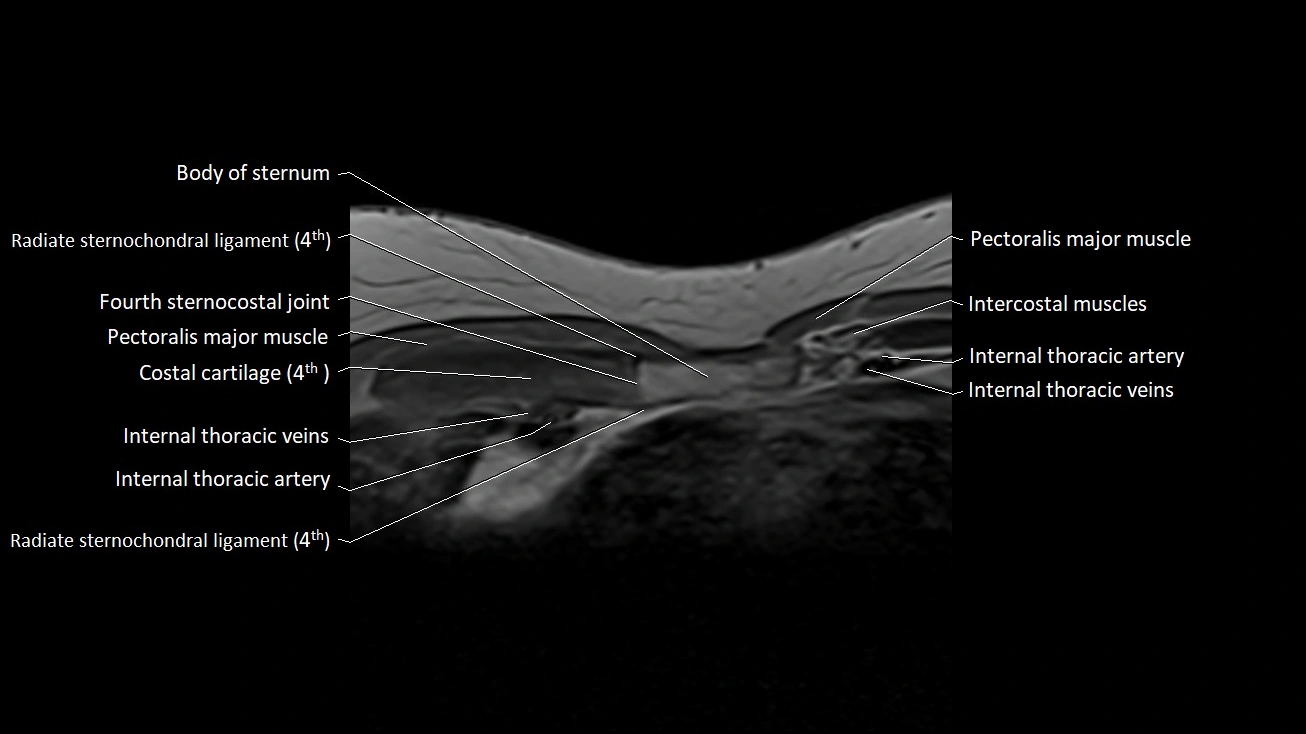

MRI images

image